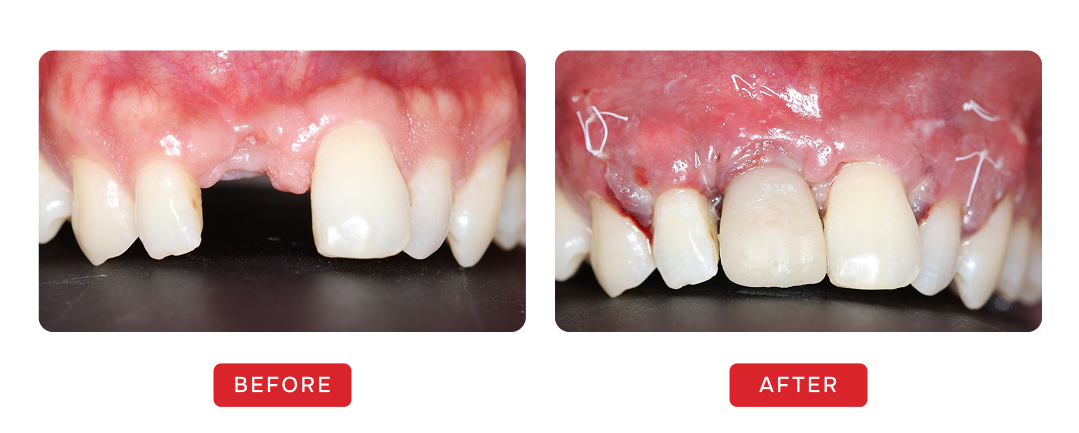

Before & After Transformations

Smile Gallery

Smile Journey Highlights